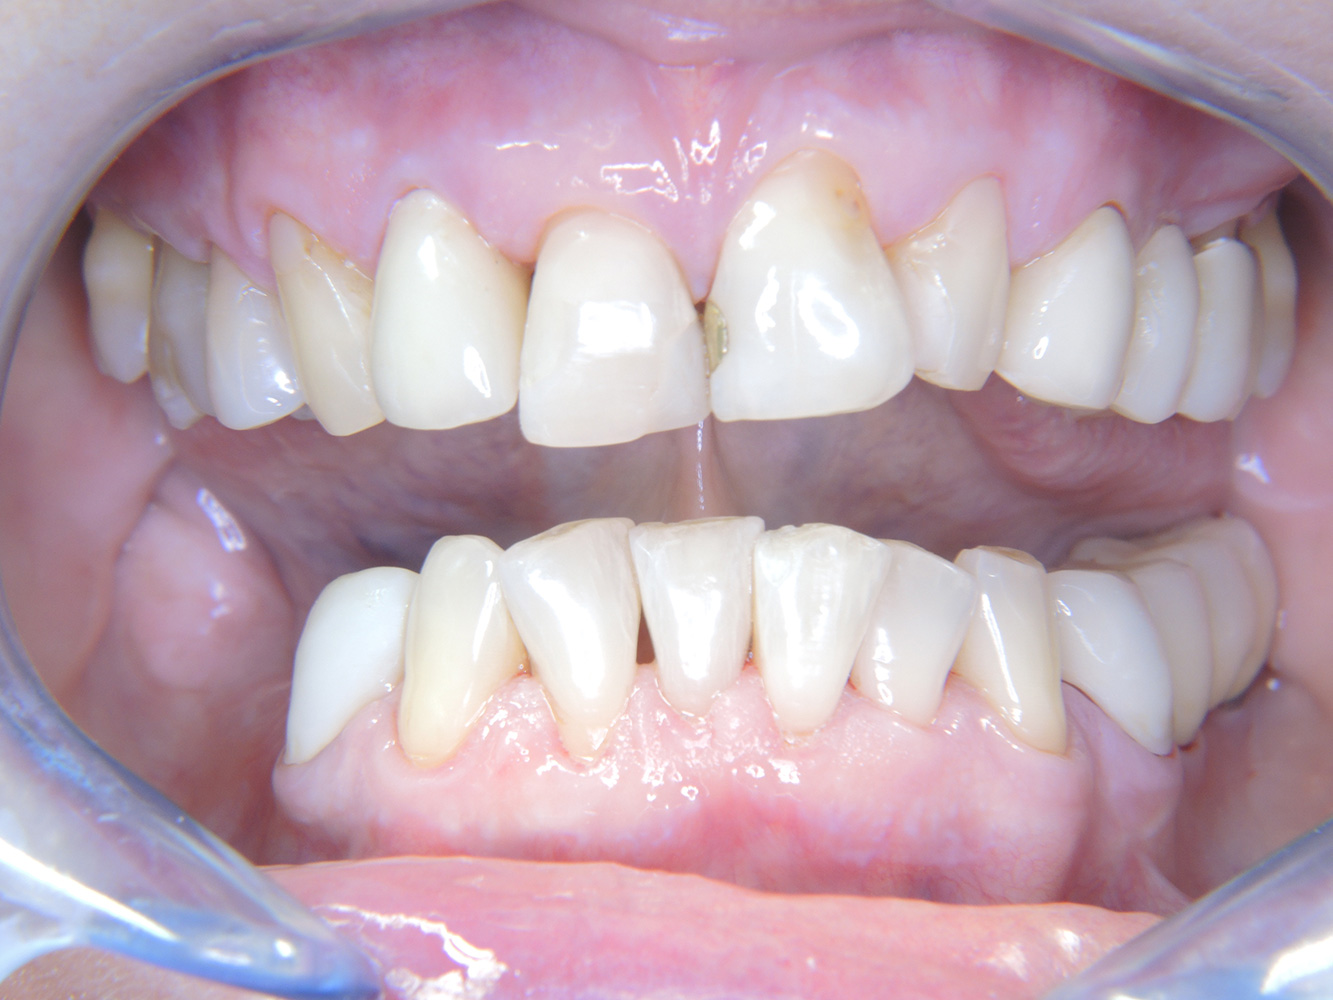

Die 68-jährige Patientin hat keine zahnmedizinisch relevanten allgemeingesundheitlichen Vorerkrankungen oder Medikation, auch aus dem Lebensstil ergibt sich kein besonderes Risiko. Die Patientin hat zwei Implantate (3. Quadrant, seit fünf Jahren) sowie eine parodontale Vorerkrankung (Parodontitis Stadium IV, Grad B) mit Zahnverlust. Derzeit zeigen sich stabile parodontale Verhältnisse, jedoch erhöht Parodontitis maßgeblich die biologischen Komplikationen bei Implantationen und es droht der Implantatverlust (21).

Trotz der stabilen Verhältnisse sollten auch bei dieser Patientin die Motivation/Instruktion nicht vernachlässigt werden. Besonderes Augenmerk gilt dem Erlernen der richtigen Implantatpflege. Gerade hier kann eine gute häusliche Pflege einen wichtigen Anteil an der langfristigen Stabilisierung der Mund- und Implantatgesundheit haben.